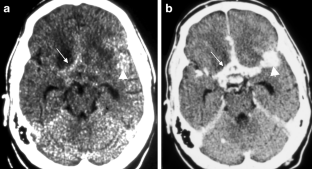

The CNS TB can be manifested (1) diffuse as tuberculous meningitis (TBM), (2) localized as tuberculoma or (3) tuberculous abscess or (4) in extradural and intradural spinal infections. Information on clinical presentation, underlying pathology and the distinguishing features is demonstrated. The TBM is further described, which may lead to cranial nerve palsy, hydrocephalus and infarction due to associated arteritis of the basal perforators. The differential diagnoses are vast and include other infections, such as bacterial, viral or fungal meningoencephalitis, malignant causes or systemic inflammation with CNS. Complicating factors of diagnosis and treatment are HIV coinfection, multi-drug resistance and TB-associated immune reconstitution inflammatory syndrome (IRIS).